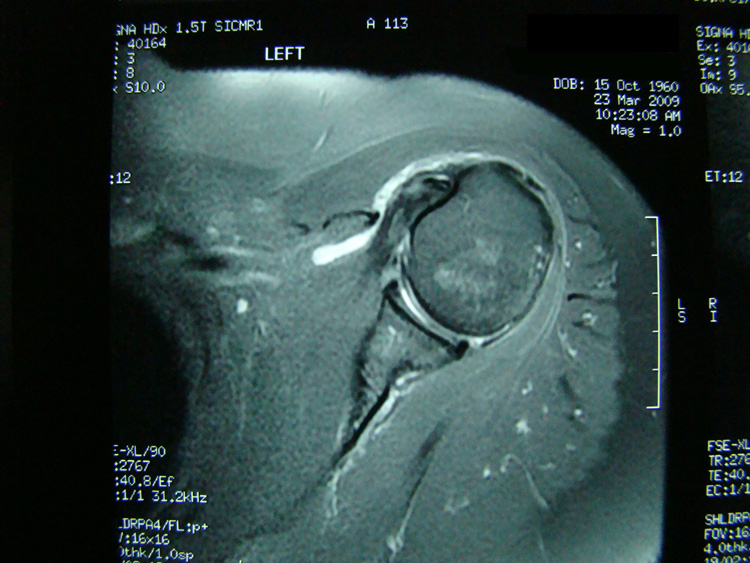

This patient presented with shoulder pain that interfered with work and exercise. The visible fluid-filled cysts on the “Before" MRIs are from chronically injured rotator cuff tendon roots.

The patient underwent treatments of a highly specialized fine-needling technique pioneered by Dr. Tallman.The follow-up MRI was done 2 months after his 6th treatment. He was released with a pain-free, full range of motion with unrestricted activities.